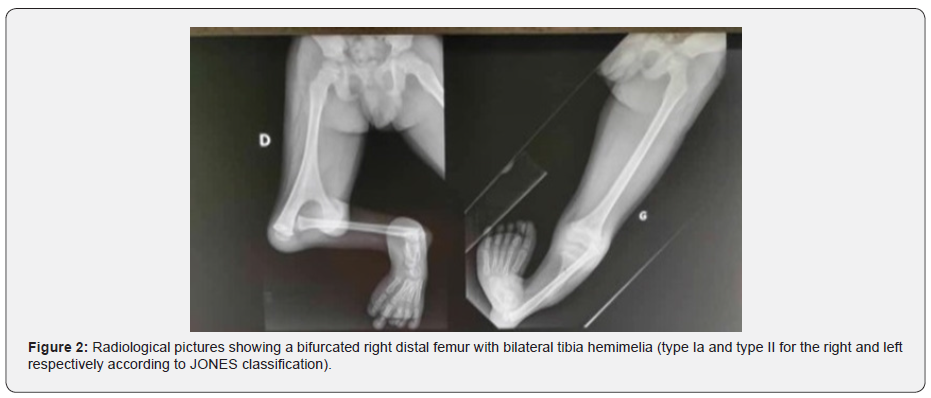

He had good capillary filling and sensations were intact. Passive and active hip movements were normal. The hip and thigh of the left lower limb looked well, and there was active knee extension with full range of motion. The left leg was shortened, and the foot had a cavovarus deformity with normal toes (Figure 1). Radiographic films (Figure 2) showed a bifurcated right distal femur with bilateral tibia hemimelia (type Ia and type II for the right and left respectively according to JONES classification).